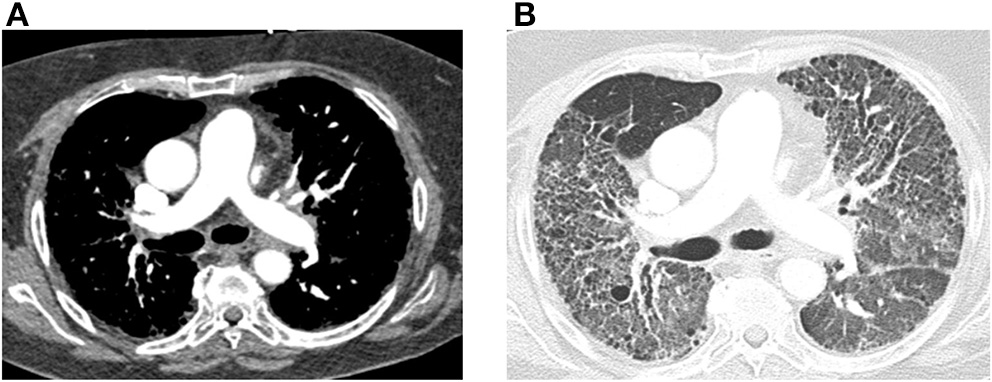

Acquiring a non-contrast chest CT scan is part of the standard workup for the diagnosis of PH (10). The presence of lung disease on a chest CT along with abnormalities on pulmonary function tests can indicate PH secondary to lung disease (Group 3 PH). Along with its evaluation of the pulmonary parenchyma, there are several findings that can screen for PH on CT. These include the absolute size of the main pulmonary artery and its relative size compared to the aorta. Chest CT with contrast is also essential if acute pulmonary embolism is suspected as an etiology of PH. New CT techniques such as dual energy CT are also being investigated to measure lung perfusion qualitatively and quantitatively. A representative image from a patient with connective tissue disease- associated interstitial lung disease and mixed PH is shown in Figure 2.

Figure 2

Computed tomography (CT) images of the chest with and without contrast are shown from a 64-year-old female with connective tissue disease, severe interstitial lung disease, and mixed severe pulmonary hypertension are shown. (A) Transaxial images are shown demonstrating an enlarged main pulmonary arterial size at 3.2 cm when compared to ascending aorta size of 2.9 cm at the same level suggestive of pulmonary hypertension. There is no evidence of pulmonary embolism with optimal contrast opacification. (B) Transaxial images in the lung window demonstrate extensive bilateral diffuse groundglass opacities and honeycombing. There is associated intralobular and interstitial thickening and bronchiectasis consistent with patient's known history of connective tissue disease associated non-specific interstitial pneumonitis.